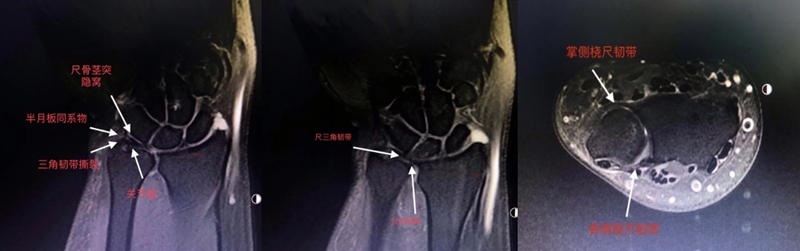

(2)MRI

ⅠA,TFCC中心穿孔,A、B三角软骨盘正常弓形低信号缺损;C轴位显示三角软骨盘中心的高信号区与D关节镜一致

ⅠB,TFCC尺侧撕裂;TFC尺侧附着处信号增高

ⅠC,尺三角韧带撕裂

ⅠD,TFC桡侧撕裂,桡侧附着处及桡尺关节处信号增高

ⅡA,TFC局部变薄,但结构完整

ⅡB,TFC局部变薄,但结构完整,月骨软骨厚薄不均

ⅡC,TFC中心撕裂,月骨软化,月三角韧带完整

ⅡD,TFC中心撕裂,月骨软化,月三角韧带缺如

图30 ⅡE,TFC中心撕裂,月骨、尺骨软骨软化,月三角韧带缺如,桡尺关节骨质增生